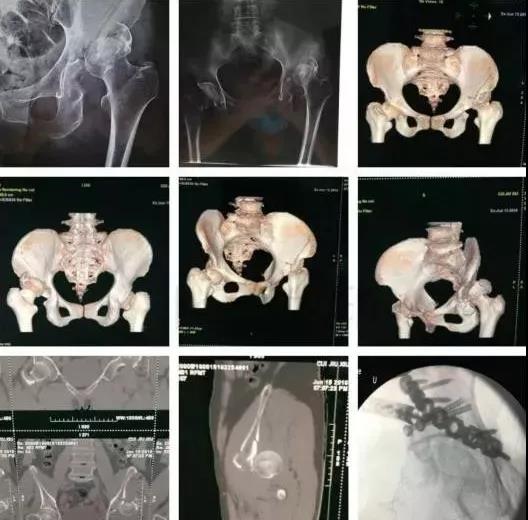

2)骨盆骨折

30min,三个决定:

- 开放性骨折,立即止血;

- 骨盆制动(10-15min);

- 观察10-15min,血流动力不稳定,能否手术?

血流动力学稳定,在7天内手术?

3)髋臼骨折(伤后5-7天)

- 人体最大的负重关节,精确复位可达到关节的最佳匹配,确保正常力学性能;

- 影像学移位程度大,不匹配>2mm--手术;

- 髋关节脱位,髋臼后壁骨折并股骨头骨折,复位后关节仍然不稳,或关节腔有游离骨块--手术。

并发症:异位骨化18-90%;股骨头坏死3-9%